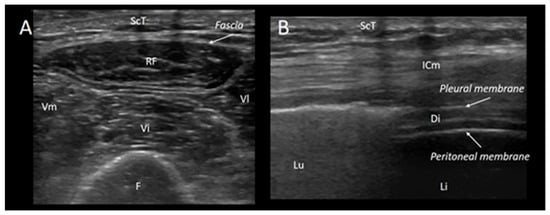

- Pillen, S.; Boon, A.; Van Alfen, N. Muscle ultrasound. Handb. Clin. Neurol. 2016, 136, 843–853. [Google Scholar]

- Kim, S.Y.; Cheon, J.H.; Seo, W.J.; Yang, G.Y.; Choi, Y.M.; Kim, K.H. A pictorial review of signature patterns living in musculoskeletal ultrasonography. Korean J. Pain 2016, 29, 217–228. [Google Scholar] [CrossRef]

- Dubé, B.P.; Dres, M. Diaphragm Dysfunction: Diagnostic Approaches and Management Strategies. J. Clin. Med. 2016, 5, 113. [Google Scholar] [CrossRef]

- Santana, P.V.; Cardenas, L.Z.; de Albuquerque, A.L.P.; de Carvalho, C.R.R.; Caruso, P. Diaphragmatic ultrasound: A review of its methodological aspects and clinical uses. J. Bras. Pneumol. 2020, 46, e20200064. [Google Scholar] [CrossRef]

- Matamis, D.; Soilemezi, E.; Tsagourias, M.; Akoumianaki, E.; Dimassi, S.; Boroli, F.; Richard, J.-C.M.; Brochard, L. Sonographic evaluation of the diaphragm in critically ill patients. Technique and clinical applications. Intensive Care Med. 2013, 39, 801–810. [Google Scholar] [CrossRef]

- Umbrello, M.; Formenti, P. Ultrasonographic Assessment of Diaphragm Function in Critically Ill Subjects. Respir Care 2016, 61, 542–555. [Google Scholar] [CrossRef]